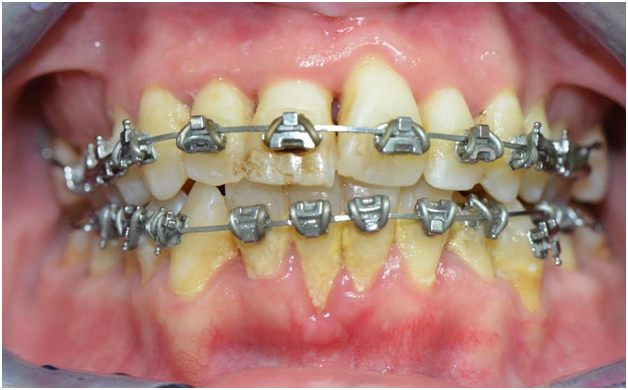

The patient received scaling and root planing followed by the application of brackets on the four maxillary anterior teeth for patient comfort (Figures 4). A subsequent appointment specifically addresses the application of brackets on the lingually inclined teeth while avoiding bracket application on labially inclined teeth (Figure 5). As the roots of previously lingually inclined teeth upright, brackets are placed on all teeth at a subsequent appointment (Figure 6). Clinical results along with photographs comparing pre and post treatment show dramatic periodontal and esthetic improvement, particularly with alveolar bone development and the reversal of recession (Figure 7). Treatment results are impressive as uprighting of the malpositioned roots creates remodeling of alveolar bone to accommodate the boney support of the properly aligned tooth. Post-treatment results also show a stable occlusion with proper overjet and overbite relations.

The successful completion of this case highlights the clinical benefits of orthodontic intervention including improved alveolar bone architecture with the reversal of gingival recession, proper root alignment, improved function, and improved esthetics. This case also showcases the capabilities of FASTBRACES ® Technologies as a safe, effective and complete treatment non-extraction both for the periodontally compromised patient and among a diverse set of clinical presentations (Figure 8).23−28

Figure 6 Bracket placement on all teeth as previously lingually inclined roots are urighted, (Courtesy of Dr. Patrick Assal, Lausanne Switzerland).

Figure 7 After resolution of Maxillary and Mandibular Orthodontosis™

and Orthodontosis™ with improved alveolar bone and gingival architecture,

(Courtesy of Dr. Patrick Assal, Lausanne Switzerland).